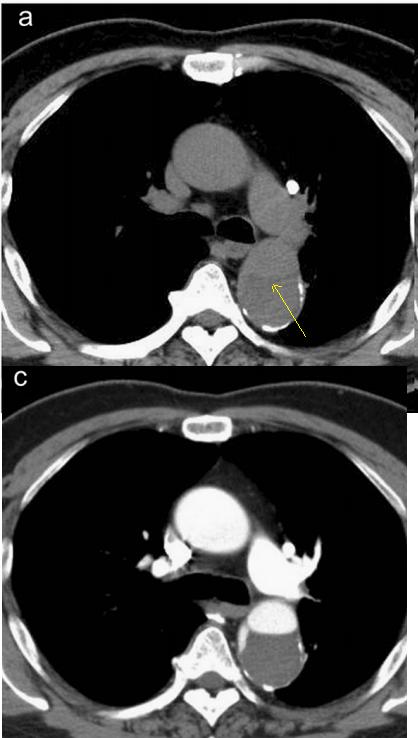

下图的胸部CT平扫,有什么致命的问题?

图7

仔细一看,主动脉里面有线样阴影!并且,线样阴影两边的密度一高一低!

图8

增强CT一看,主动脉夹层,密度相对高的是流动的血液!

图9